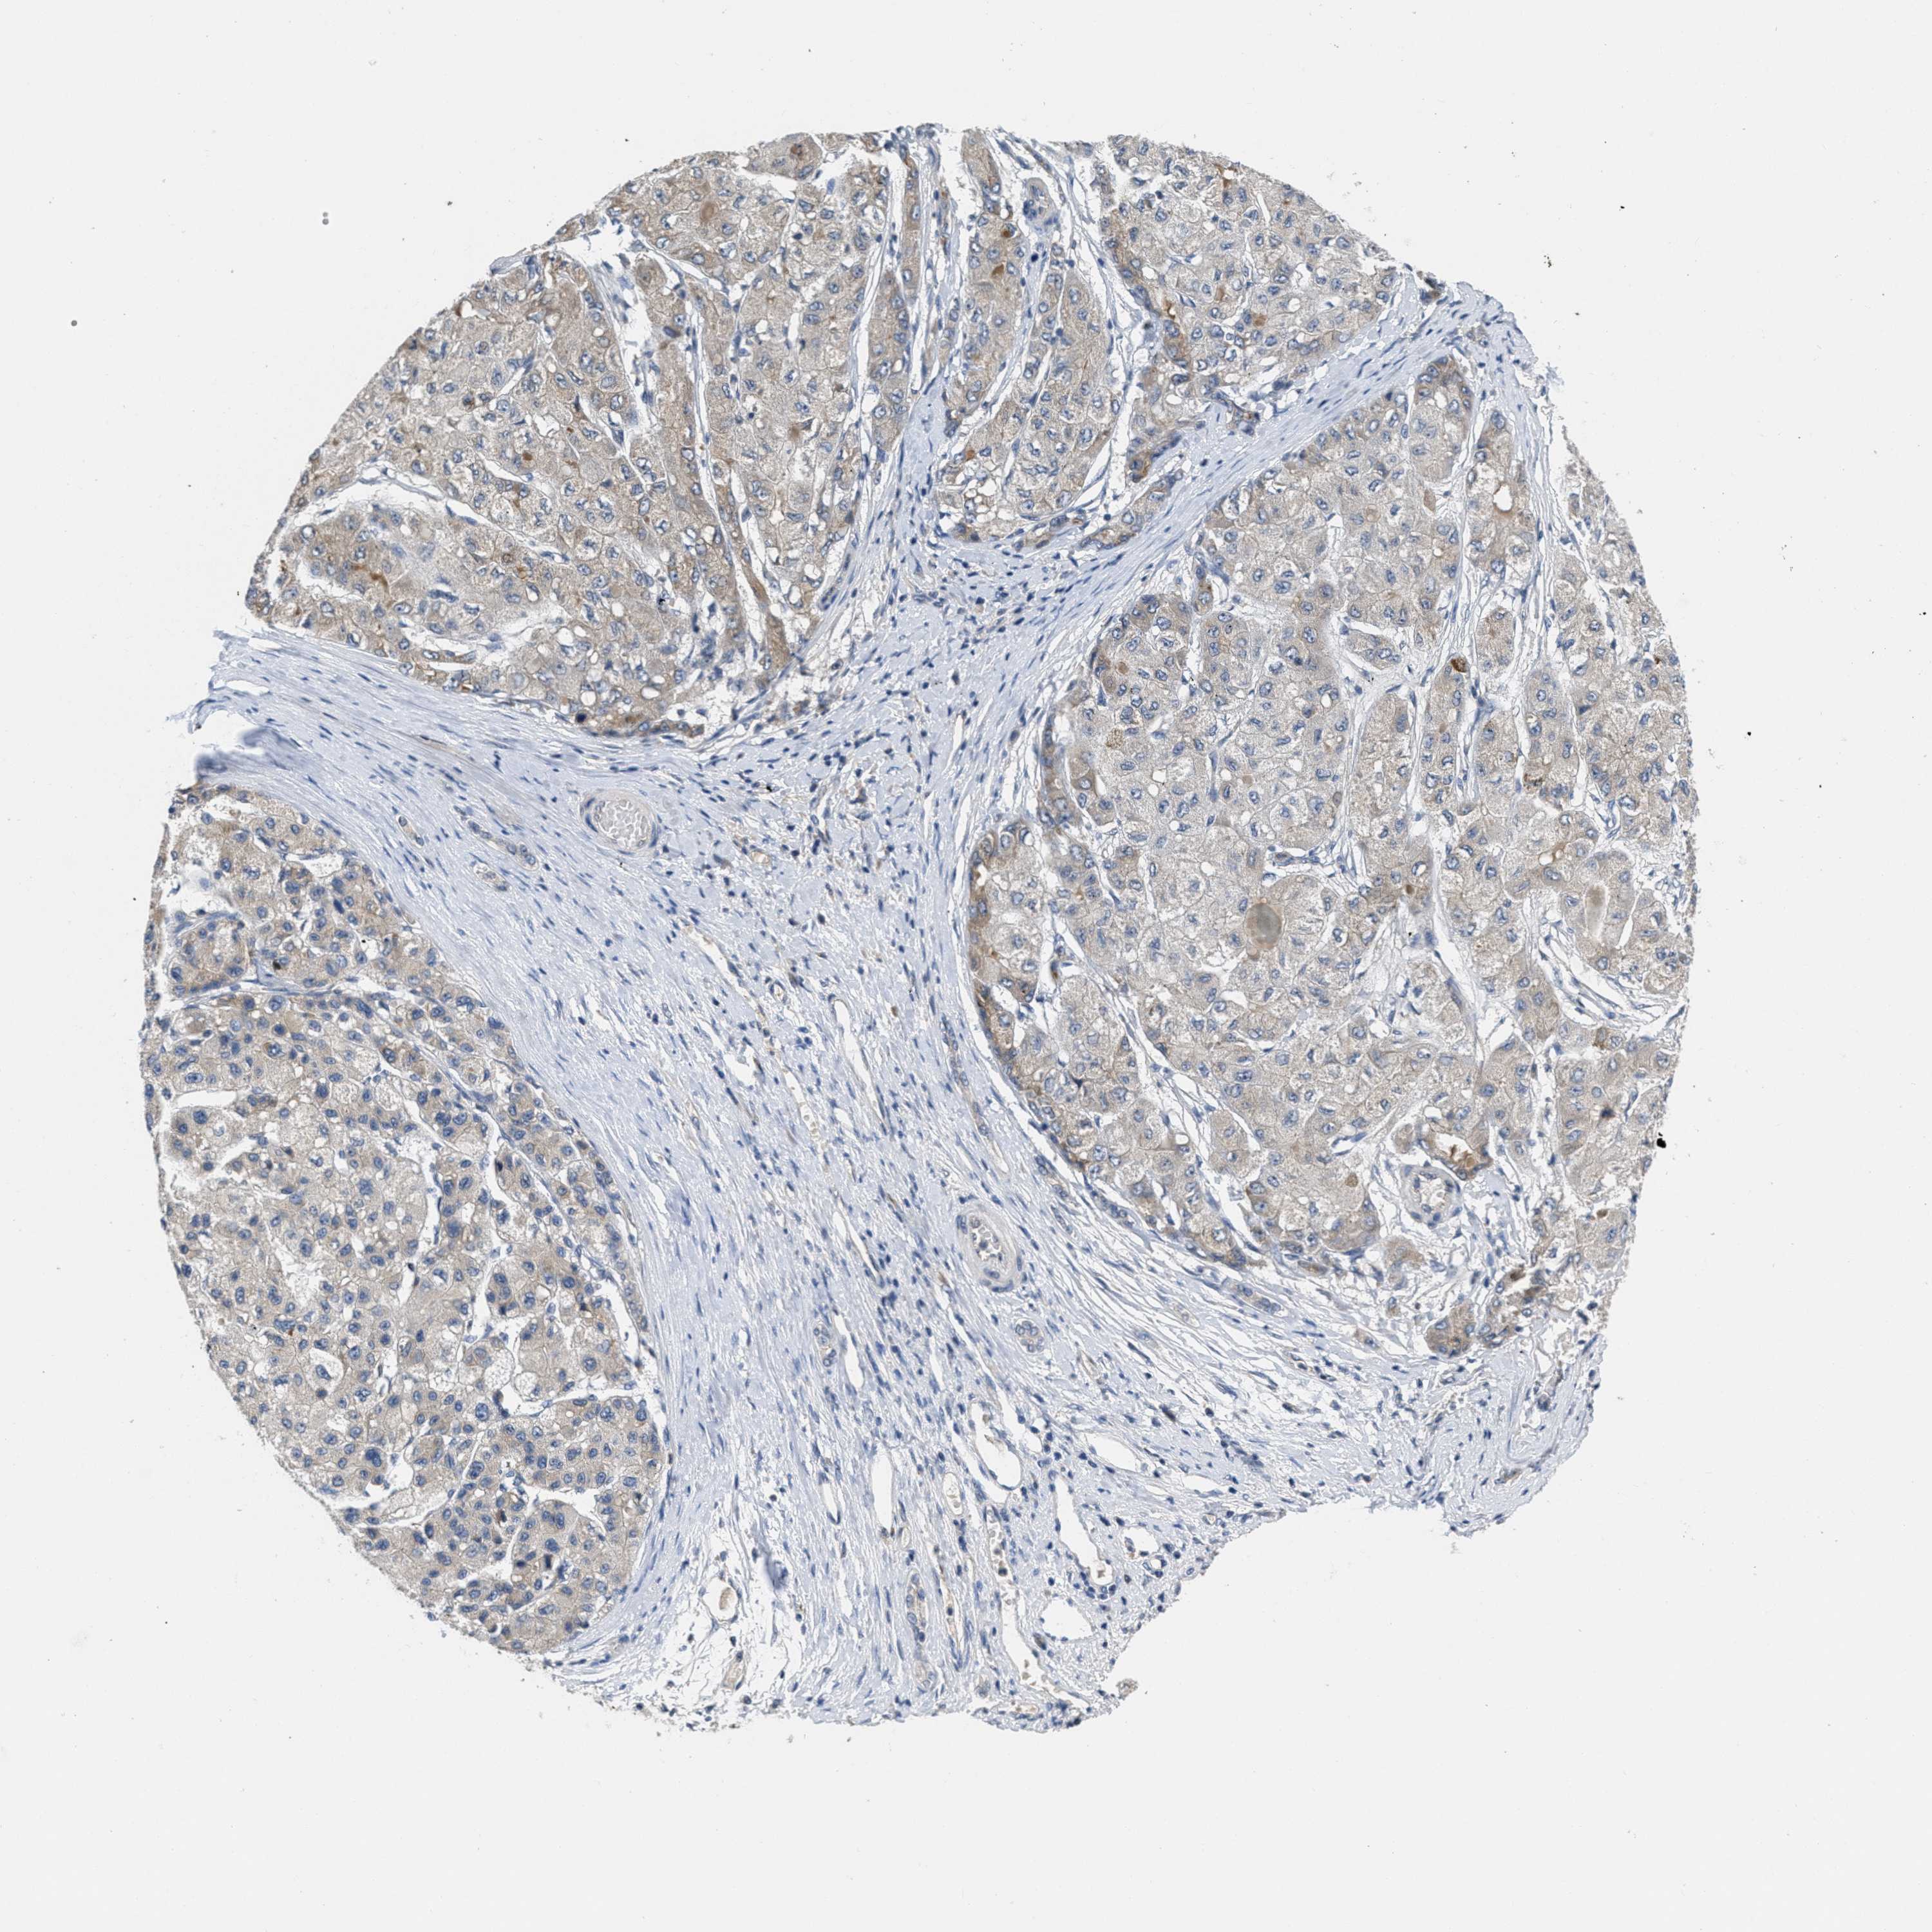

LIVER CANCER - Protein expressioni

A mouse-over function shows sample information and annotation data. Click on an image to view it in a full screen mode. Samples can be filtered based on level of antibody staining by selecting one or several of the following categories: high, medium, low and not detected. The assay and annotation is described here.

Note that samples used for immunohistochemistry by the Human Protein Atlas do not correspond to samples in the TCGA dataset.

Antibody stainingi

Antibody staining in the annotated cell types in the current human tissue is reported as not detected, low, medium, or high, based on conventional immunohistochemistry profiling in selected tissues. This score is based on the combination of the staining intensity and fraction of stained cells.

Each image is clickable and will lead to virtual microscopy that enables deeper exploration of all samples and also displays staining intensity scores, fraction scores and subcellular localization as well as patient and tissue information for each sample.

Antibody HPA018793

Antibody HPA018816

Antibody CAB017815

Staining

High

Medium

Low

Not detected

Intensity

Strong

Moderate

Weak

Negative

Quantity

>75%

75%-25%

<25%

None

Location

Nuclear

Cytoplasmic/membranous

Cytoplasmic/membranous,nuclear

Carcinoma, Hepatocellular, NOS

Cholangiocarcinoma